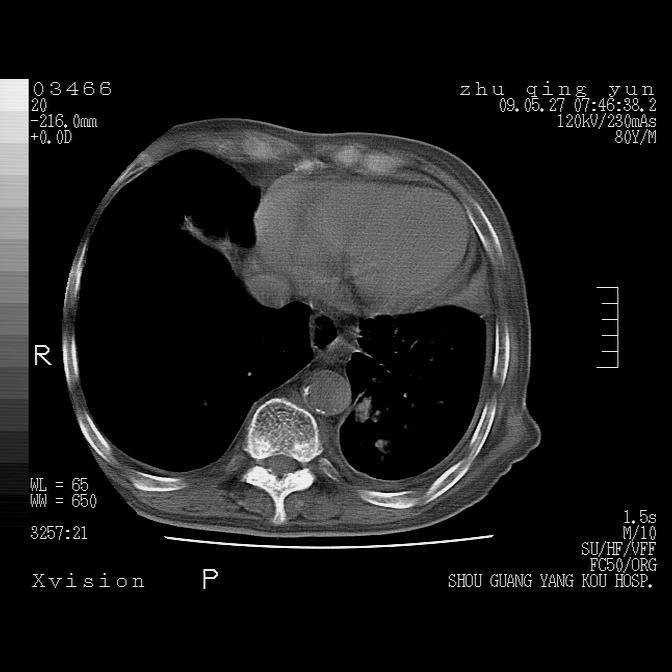

病人男性,年龄80,气喘来院,其他病史不太详细,1月前有过恶心,呕吐,在当地人民医院做过钡餐,诊断胃炎,

1)考虑左肺中央型肺癌并阻塞性肺炎,后下纵隔受侵伴纵隔淋巴结转移。2)双侧少量胸腔积液,胸膜增厚。3)心包积液。

左肺下叶见多发片状及结节状病灶,左肺基底段支气管闭塞,纵隔内见多发淋巴结肿大,纵隔向左侧移位,左侧胸廓变小。应该是左肺下叶中心型肺癌,纵隔淋巴结转移,左侧肺内转移,左肺基底段肺不张,阻塞性肺炎。

1)考虑左肺中央型肺癌并左肺下叶阻塞性肺炎、不张;左胸膜腔积液、心包积液、纵隔淋巴结转移;癌肿累及左心房。2)左心室大。冠状动脉壁钙化斑。

考虑左下肺中心性肺癌伴阻塞性肺炎,纵隔淋巴转移,左侧胸膜及心包转移。